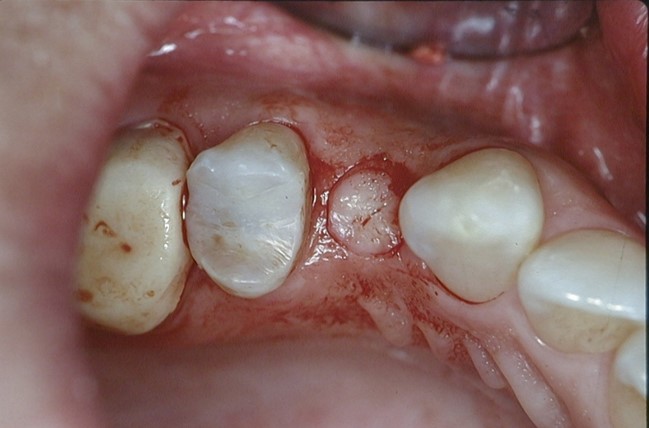

شکل فوق روش پانچ را نشان میدهد که در آن بخشی از لثه پانچ شده و برداشته میشود.

در روش پانچ، به جای برش لثه با تیغ جراحی و کنار زدن آن، با یک وسیله گرد کوچک (پانچ) یک سوراخ دایرهای معمولا به قطر 5-4 میلیمتر در لثه ایجاد میشود و در واقع قسمتی از لثه کاملا برداشته شده و حذف میشود تا محل کاشت ایمپلنت در استخوان نمایان شود.

در این روش، لثه به صورت کامل کنار زده نمیشود و جراحی بدون بخیه و با کمترین دستکاری بافت نرم انجام میگیرد.